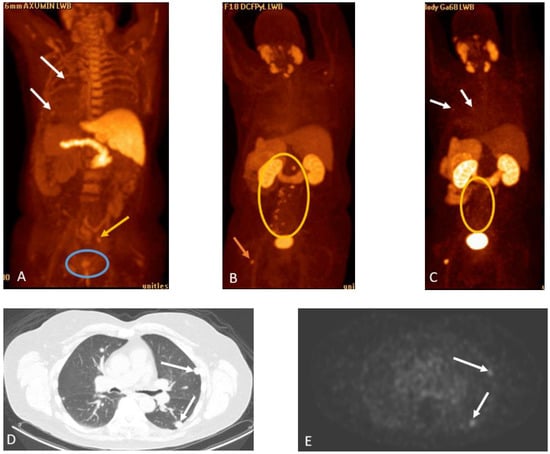

Detection of Loco-Regional Disease and Distant Metastases